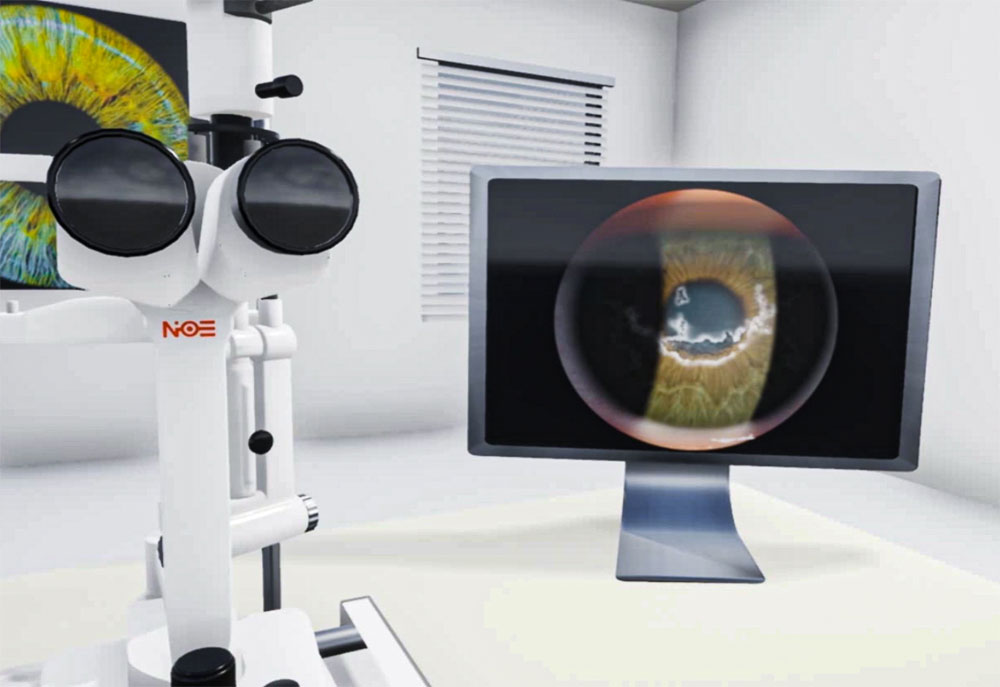

Внедрение витреоретинальной хирургии, создание лазерного офтальмологического центра